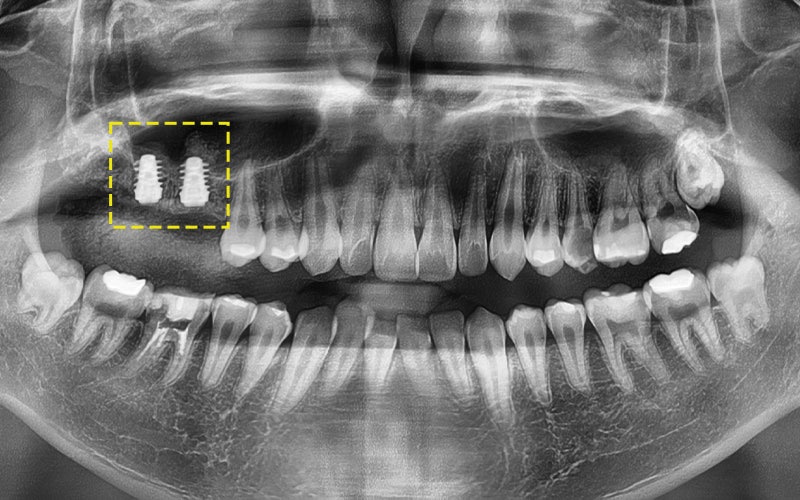

2025.06.18

구강 내 상황을 면밀하게 고려하여

올바른 위치 및 방향대로

임플란트를 잘 식립해주었답니다!

그래서 저희는 세계에서 가장 오래 쓰이는,

그리고 가장 튼튼하다고 인정받는

스위스 스트라우만 임플란트를 추천드렸고

수술을 진행하였습니다!